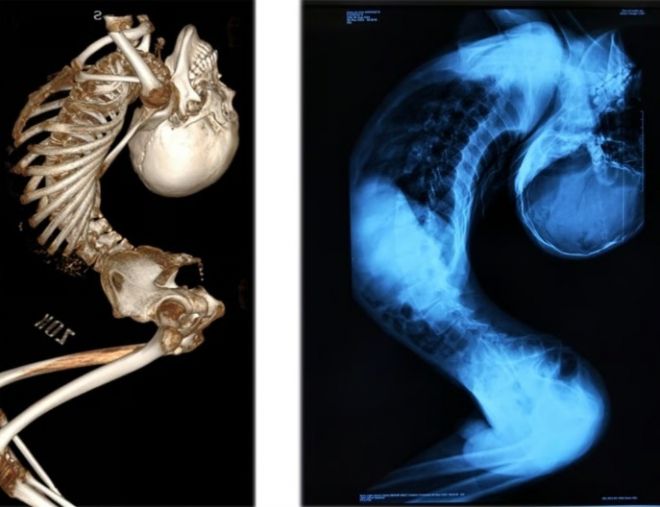

중국 산둥성 출신인 장씨는 척추 관절과 인대에 심각한 염증을 일으키는 희귀 질환인 ‘강직성 척추염’을 앓아 목과 척추가 뒤로 심하게 굽은 채 살아왔다.

이 희귀한 질환으로 인해 그의 몸은 ‘Z자’ 형태로 접혀 머리와 엉덩이 간격은 손바닥 한 뼘에 불과했고, 접힌 키는 80cm에 불과했다.

이후 지난해 8월 그는 청두의 척추 교정 권위자인 량이젠 교수에게 경추·흉추·요추 절골술과 고관절 교정 등 총 4차례의 대수술을 받았다.

지난 6월 받은 마지막 수술은 12시간 넘게 이어졌으며, 그의 척추는 약 170도 교정됐다.